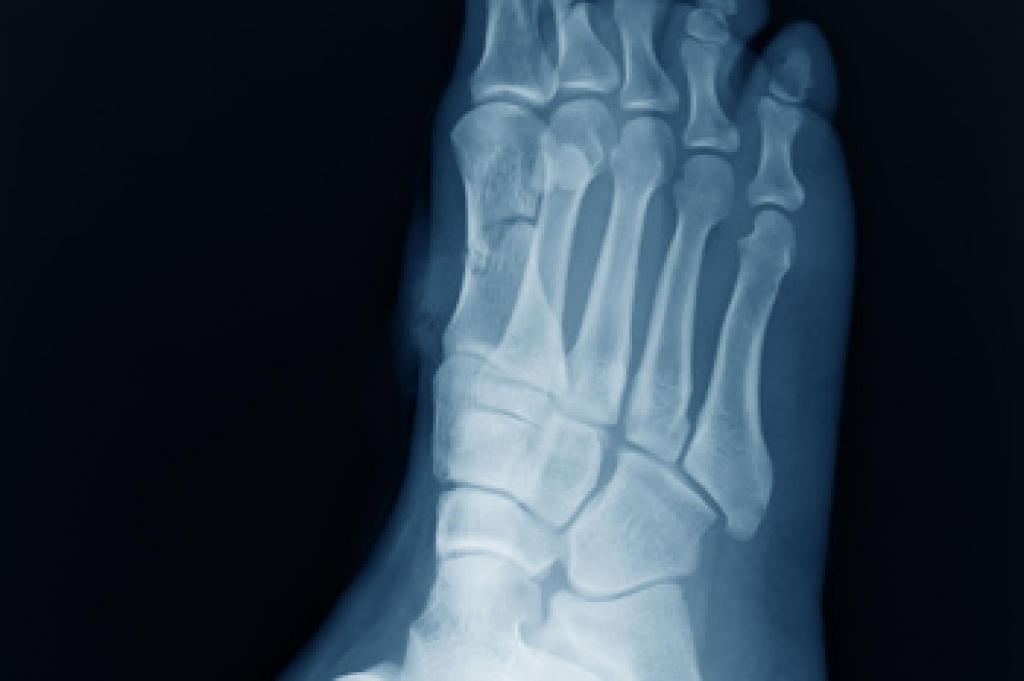

To figure out the cause of foot pain, podiatrists utilize several different methods. This can range from simple visual inspections and sensation tests to X-rays and MRI scans. Prior medical history, family medical history, and any recent physical traumatic events will all be taken into consideration for a proper diagnosis.